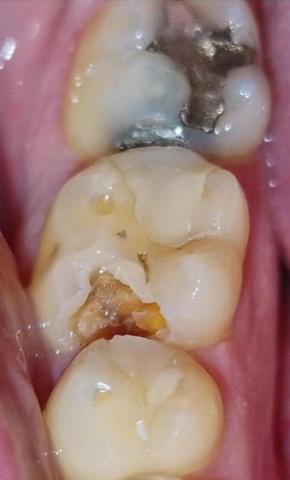

The image shows posterior molar teeth with visible tooth decay and a failing restoration. One tooth has a large cavity with exposed dentin, while the adjacent tooth shows an old metallic filling with possible marginal breakdown.

Large open cavity on the chewing surface of a molar

Visible brown and yellow decayed dentin

Loss of enamel structure

Adjacent molar has an old metallic (amalgam) filling

Possible leakage around the filling margins

Gum tissue nearby appears mildly irritated

Food retention area present inside the cavity